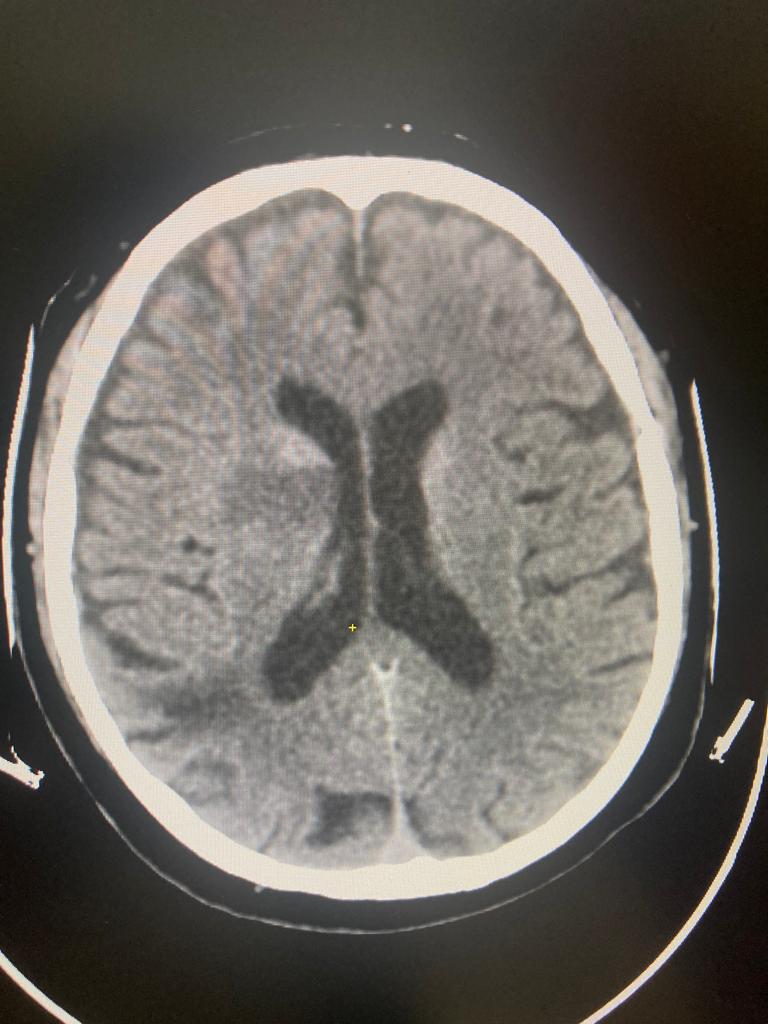

Внутричерепная гипотензия: КТ-исследования и их интерпретация

Раздел: Образы вокруг